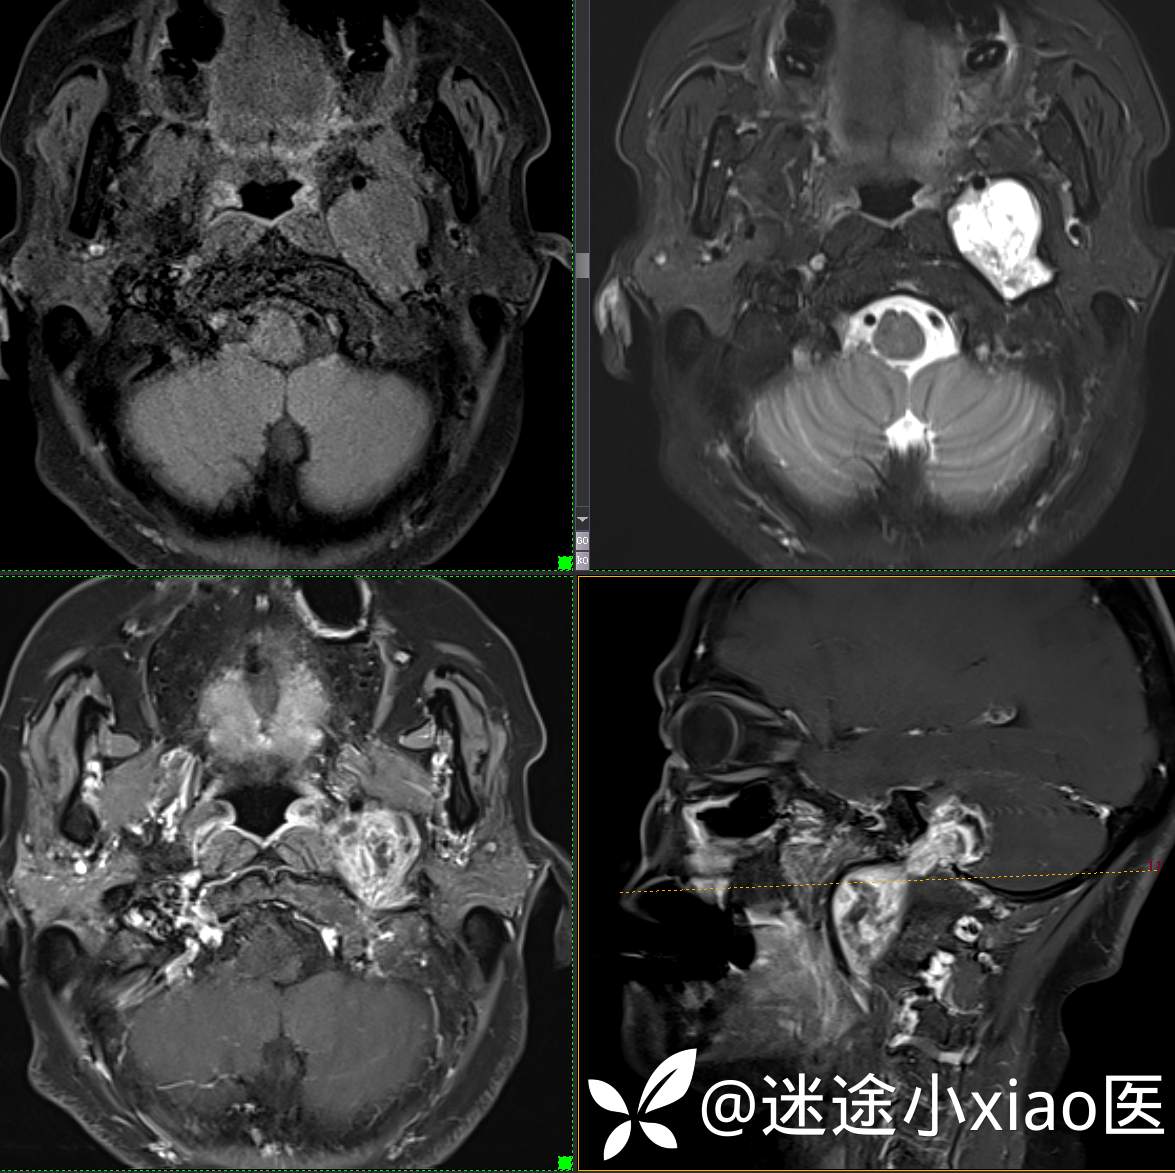

头颈组17:颈静脉孔区占位,副神经节瘤?神经鞘瘤?脑膜瘤?

患者性别:女

患者年龄:57岁

主 诉:  声音嘶哑进食困难伴左侧颌部麻木半年

现病史:  【患者半年前无明显诱因出现声音嘶哑,进食困难,只能进食糊状食物,伴有恶心呕吐,无明显头痛头晕,未加重视。

神经鞘瘤 (117)